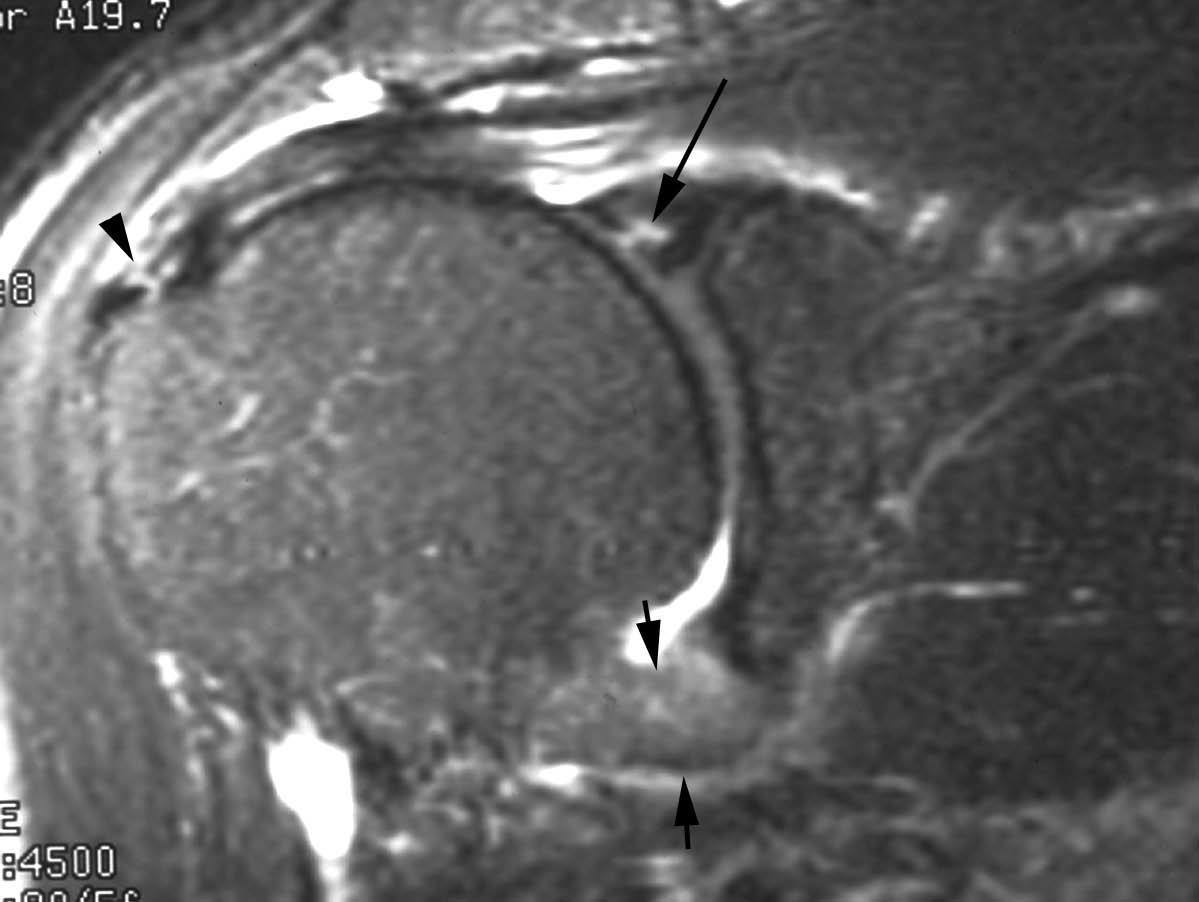

Lesiones por pinzamiento posterosuperior (posterosuperior impingement syndrome) < del LG superior con extensión posterior (SLAP tipo II-b), roturas parciales o completas del tendón del supraespinoso y pequeñas fracturas por compresión del margen posterosuperior del trocánter. Estas lesiones se producen típicamente en el atleta lanzador.

La etiología y el mecanismo de producción de estas lesiones han sido ampliamente debatidos. Jobe et al en 198930 consideraron que estas lesiones eran debidas a una laxitud de la cápsula anterior que producía una migración anterior de la cabeza humeral durante la abducción y rotación externa. En 1991, Walsh et al31, siguiendo la teoría de Jobe et al30, describieron el síndrome de pinzamiento interno o posterosuperior relacionado con una laxitud capsuloligamentosa anterior. En 1998, Burkhart et al describieron una alta incidencia de SLAP II-b en el atleta lanzador32. Estos mismos autores llegaron a la conclusión en el año 200333 de que las lesiones descritas anteriormente son producidas por una cascada de eventos originados por una fibrosis y engrosamiento de la cápsula posteroinferior y de la banda posterior del LGHI. Según estos autores, el atleta lanzador, después de múltiples movimientos de abducción y rotación externa, consigue un desplazamiento del punto de rotación y del arco de traslación del trocánter desde el centro de la cavidad glenoidea hacia arriba y hacia atrás «la zona» tal como se describe anteriormente (microinestabilidad). Todo ello conduce a un engrosamiento de la cápsula posterior que evoluciona a una restricción de la rotación interna (fig. 34). A esta restricción se la considera el punto de origen de la cadena de lesiones que conducen a lo que se llama el «brazo muerto» (the dead arm) que representa el final de una carrera profesional deportiva. La restricción de la rotación interna se la conoce bajo las siglas de GIRD (glenohumeral internal rotation deficit). Sin embargo, no queda claro si la traslación posterosuperior del centro de rotación en el atleta sucede antes o después de la formación de cicatriz y engrosamiento capsular posterior.

Cuando el deportista consigue crear, a través del entrenamiento, este desplazamiento posterosuperior del centro de traslación o bien tiene lugar a través del engrosamiento de la cápsula posteroinferior, el hombro llega a conseguir una rotación externa de más de 150 grados en abducción a 90 grados. En este momento se llega a un punto crítico, en el cual la tensión que se produce a nivel de la inserción del TLB, en el borde superior del LG, conduce a un «arrancamiento» del mismo, con extensión de la lesión hacia la parte posterior (SLAP II-b); a este mecanismo se le conoce como peel back (fig. 35).

Una vez que se ha producido la lesión SLAP II-b, la continuación de las fuerzas de extrema rotación externa conducen a una torsión repetitiva del tendón supraespinoso, que lleva a una rotura parcial o completa del mismo (fig. 36).